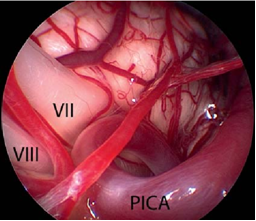

面神经的微血管减压术是治愈面肌痉挛的唯一治疗选择。手术旨在去除出脑干区(REZ)血管对神经的压迫。血管对神经造成压迫是主要病因。手术需全身麻醉。为了观察手术过程中耳蜗的和面部的神经的改变,需要在手术进行过程中对面神经的肌电图(EMG)和听觉诱发电位(auditory evoked potentials)进行监测。使用乙状窦后入路开颅术(retrosigmoidal craniotomy)(figure 3)暴露小脑桥脑角。在随后的手术过程中,尤其注意检查出脑干区的面神经(figure 5),该面神经发源于脑干。内窥镜检查法对于确定血管压迫位置很有效(figure 4,6)。因此,在米兰·(milan)医院把内窥镜检查法作为指导程序。

Figure 4内窥镜图像(使用30°内窥镜拍摄)显示了出脑干区的蜗神经和面神经的临近部位,它们被小脑后下动脉(PICA)环所压迫(与figure 2是同一患者)

Figure 5小脑桥脑角区解剖示意图:Ⅴ=三叉神经;Ⅷ=蜗神经;Ⅶ=面神经;Ⅸ=舌咽神经;Ⅹ=迷走神经;Ⅺ=脊附属神经。